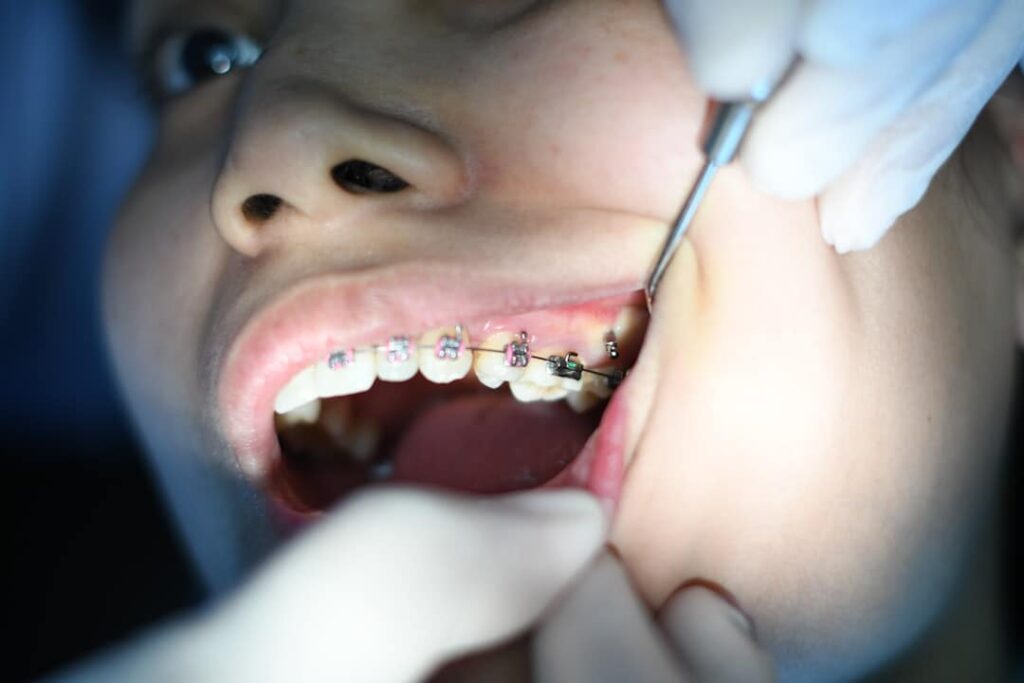

Erro Odontológico: Advogado Explica o Que Fazer.

Sofreu um erro odontológico? Entenda o que é, quais seus direitos e os passos para buscar indenização com a ajuda de um advogado especialista.